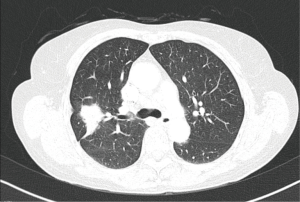

A patient, female, 61 years old, was discovered with a space-occupying lesion on the right upper lung (Figures 1,2) during the routine physical examination. She has no past medical history (PMH) of long-term chronic diseases. After knowing that this mass might be lung cancer, the patient refused aspiration biopsy and asked for a thoracoscopic exploratory surgery.